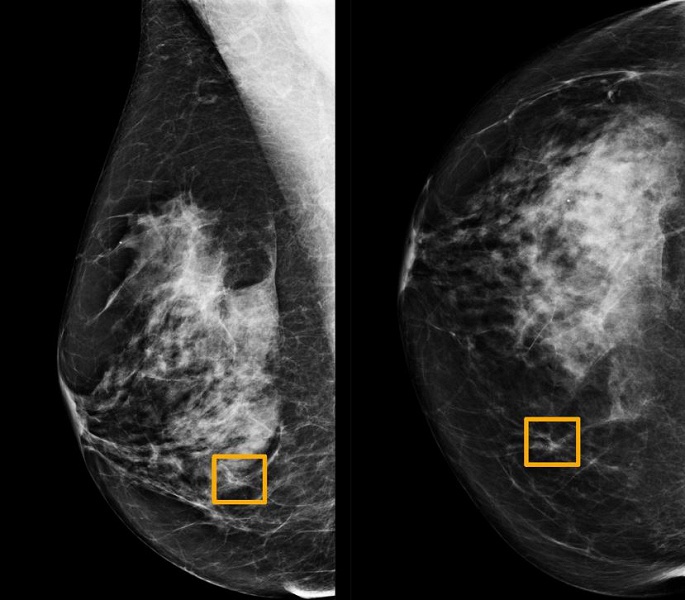

Изучая маммограммы, система искусственного интеллекта Google показала себя не хуже, чем опытные врачи и продемонстрировала перспективу уменьшения количества ошибок.

Система разработана компанией DeepMind, в 2014 году приобретенной холдингом Alphabet, совместно с Google Health. Команда, в которую вошли исследователи из Имперского колледжа Лондона и Британской национальной службы здравоохранения, провела обучение системы для выявления рака молочной железы на десятках тысяч маммограмм. Затем они сравнили результаты работы системы с фактическими результатами из набора 25 856 маммограмм из Великобритании и 3097 из США. Исследование показало, что система искусственного интеллекта может идентифицировать рак с такой же степенью точности, что и опытные радиологи, при этом уменьшая количество ложноположительных результатов на 5,7% в группе в США и на 1,2% в группе из Великобритании. Сократилось и количество ложных негативов, где тесты ошибочно классифицируются как нормальные — на 9,4% в группе из США и на 2,7% в группе из Великобритании.

Дело в том, что эти системы обучены распознавать то, что и так видят радиологи, в то время как ИИ учится распознавать рак на основе фактических результатов тысяч маммограмм и в результате может выявить тонкие признаки, которые, по словам исследователей, «не замечает человеческий глаз и мозг».